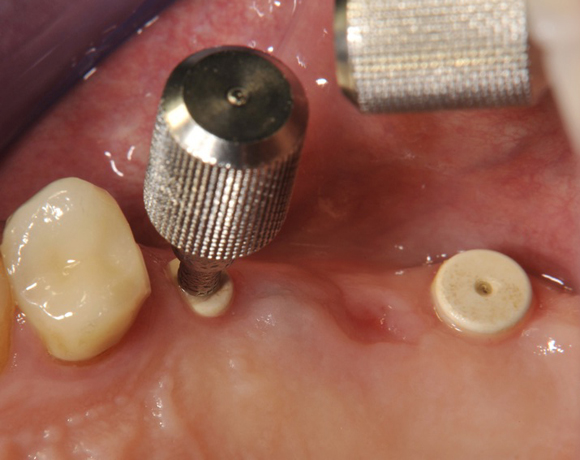

Im vorliegenden Patientenfall wurden für die Zähne 25 und 27 jeweils ein Implantat gesetzt. Nachdem die Implantate eingeheilt waren, wurde 25 – 27 mit einer Brücke versorgt.

Der operative Teil